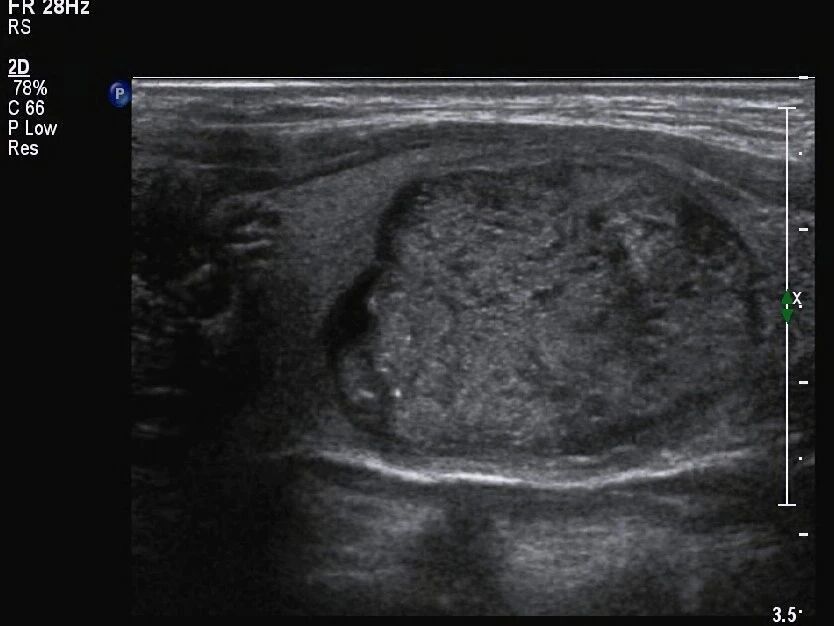

囊实性结节,存在包含液态的囊性部分,还存有含有固态的实性部分,这种具备混合结构的状况,给诊断带来特殊挑战,要留意的关键在于,其与由大量微小囊腔构成、基本没有实性成分的海绵状结节有着本质差别 。

在考量恶性风险时,结节全然呈现囊性状态,结节全然呈现海绵状模样,一般而言这种结节偏向良性,作为实性的结节,其风险相对较高,然而囊实性结节所具备的风险,处于这两者的范围区间之内,临床所获取的数据表明,囊实性结节致使恶变的概率,显著比完全呈现为实性样子的结节来得低。

结节在不同部位,那里出现了然点状强回声,而其临床意义有着截然不同的情况, 在位于囊性部分的体现为短线状强回声,尤其是伴有典型彗尾征的那种,大多是由浓缩胶质形成的,这属于良性表现,这些胶质实际上是甲状腺滤泡内浓缩的胶状性质物 。

点状强回声出现在实性部分时,此显示情况下其后方没有清楚明显的彗尾征,这时需十分密切高度警惕微钙化存在的可能性,在这样的状况下,即便结节其他特征表现展示良好,也应按可疑特征样式处理应对,还建议更进一步深入检查明确定性质,。